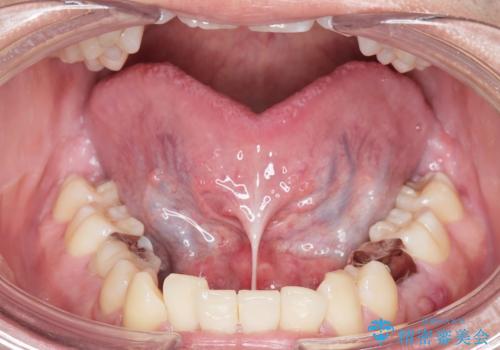

舌小帯を切りたい。

- 舌が動かしにくいと来院。

局所麻酔をし、舌小帯切除術を行うことになりました。